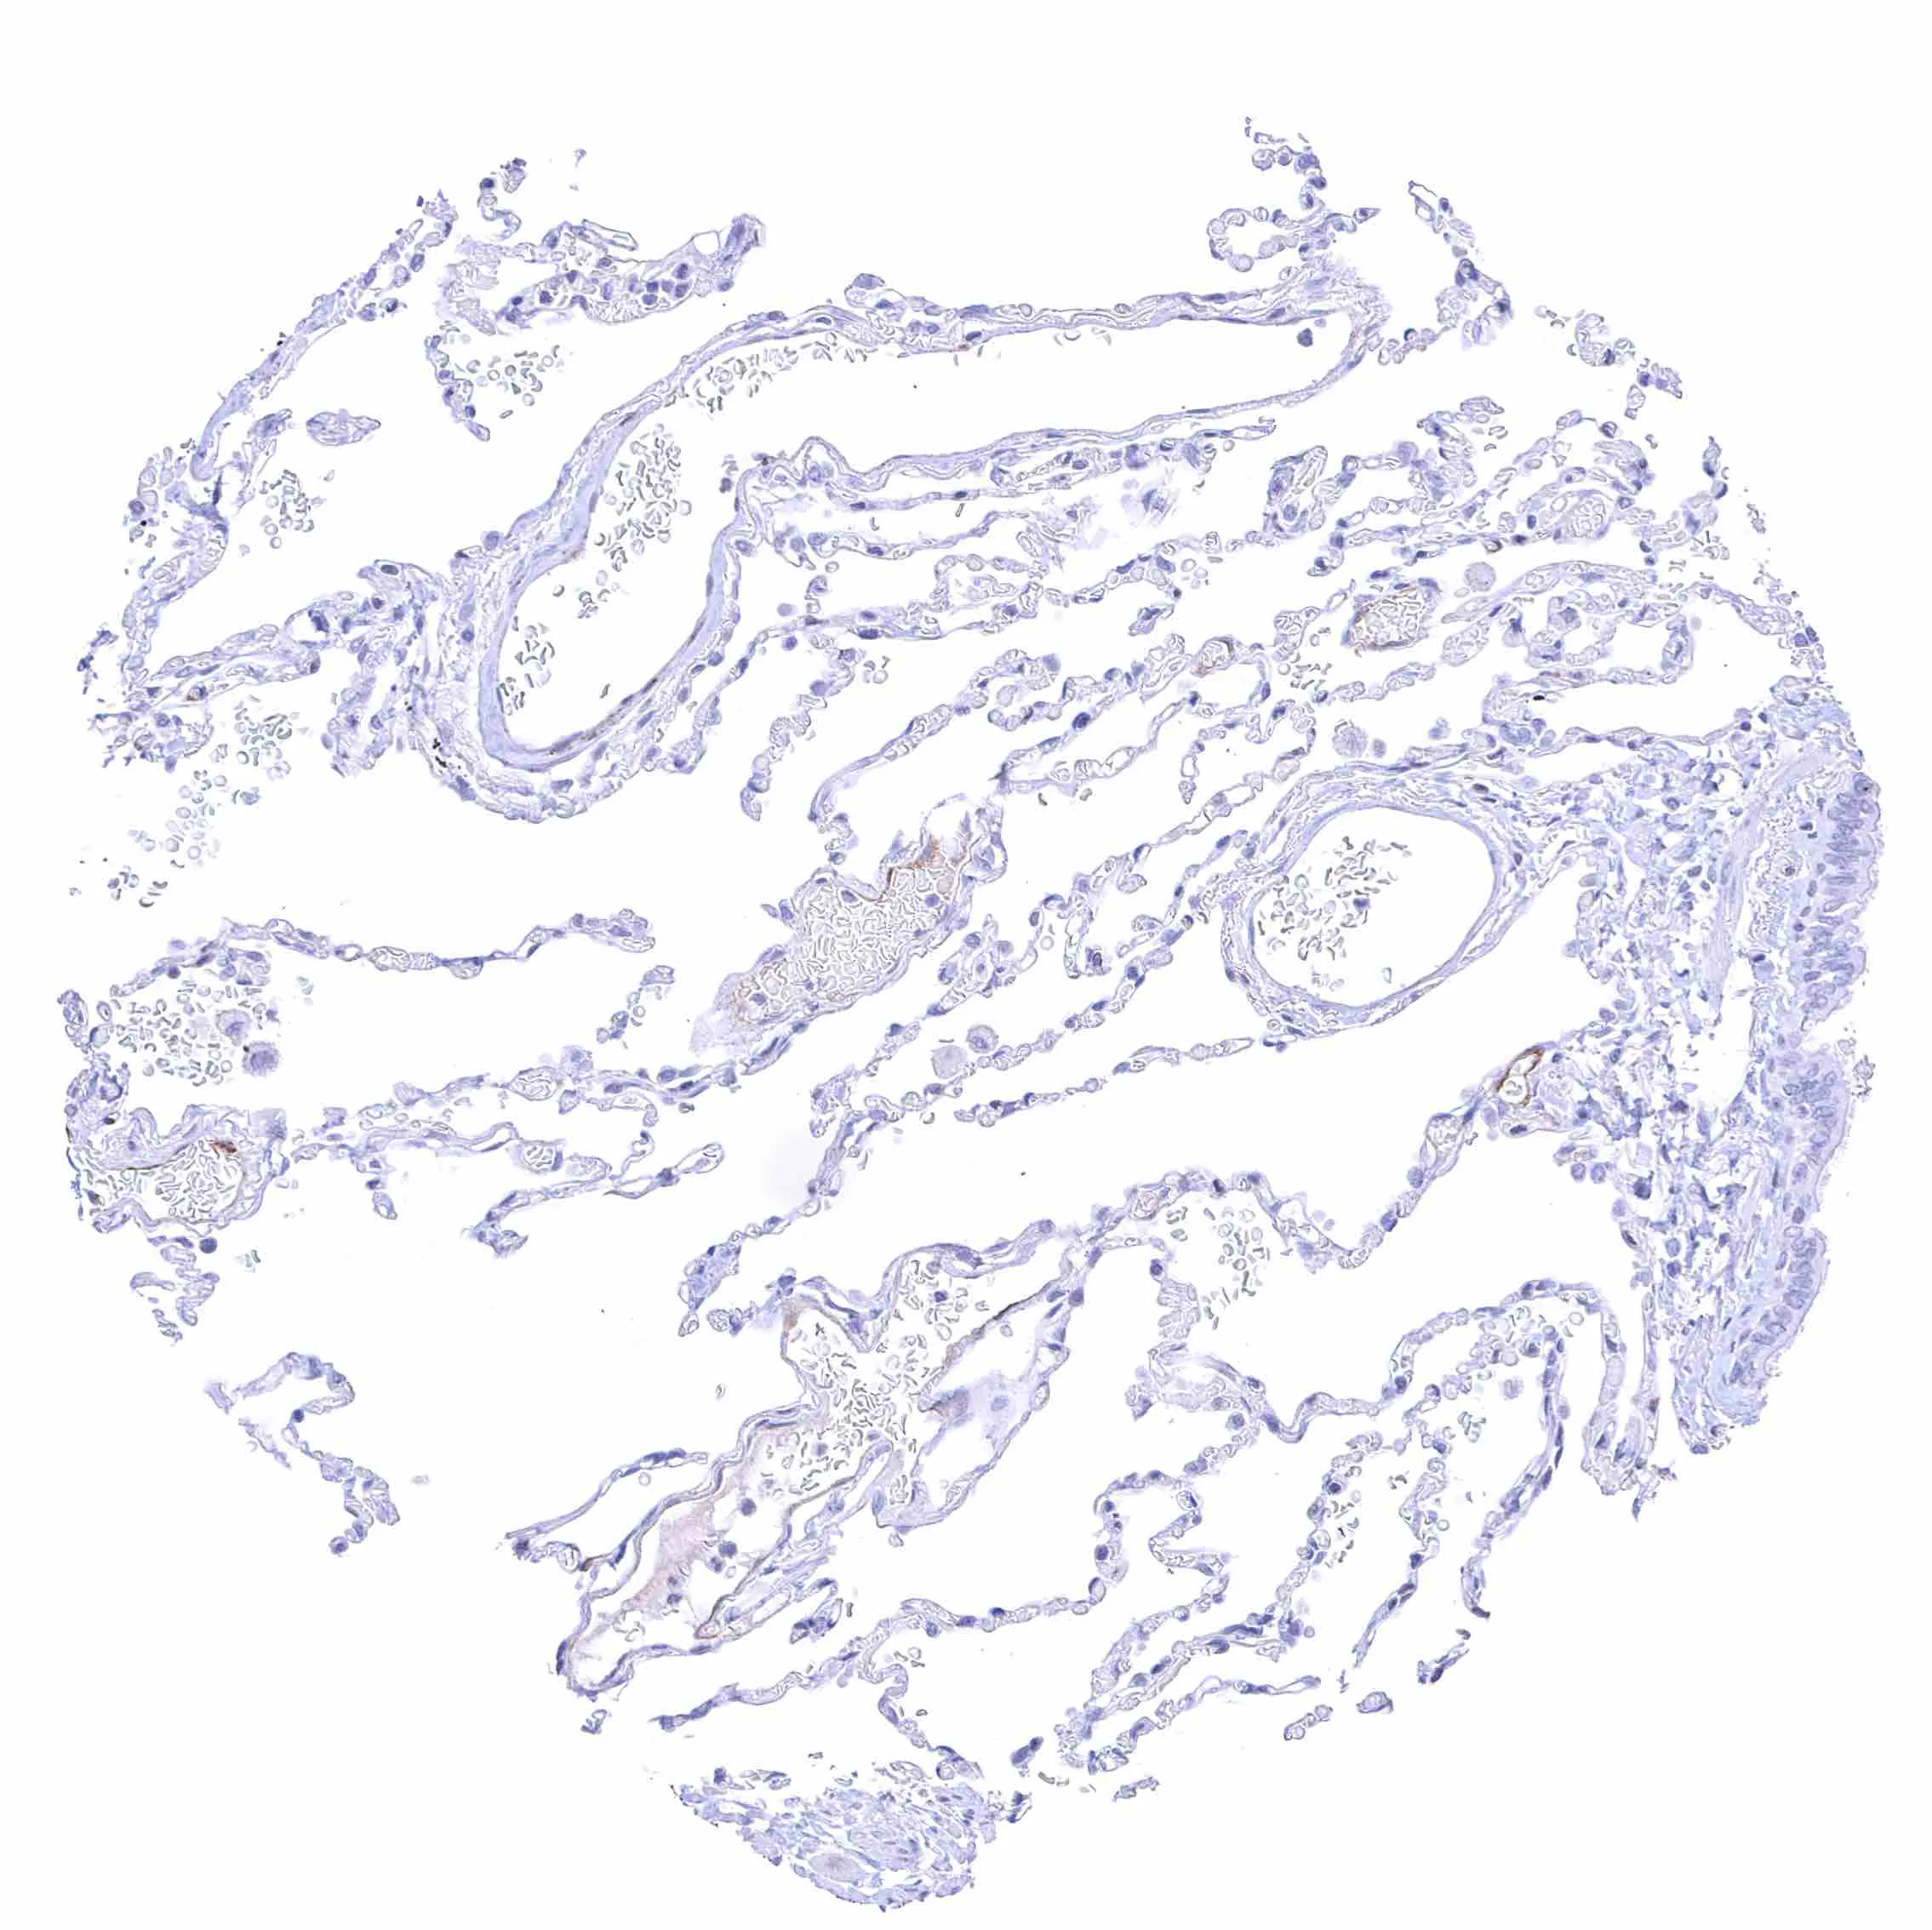

Lung – Faint membranous NPR-C staining at the luminal cell border of some endothelial cells.